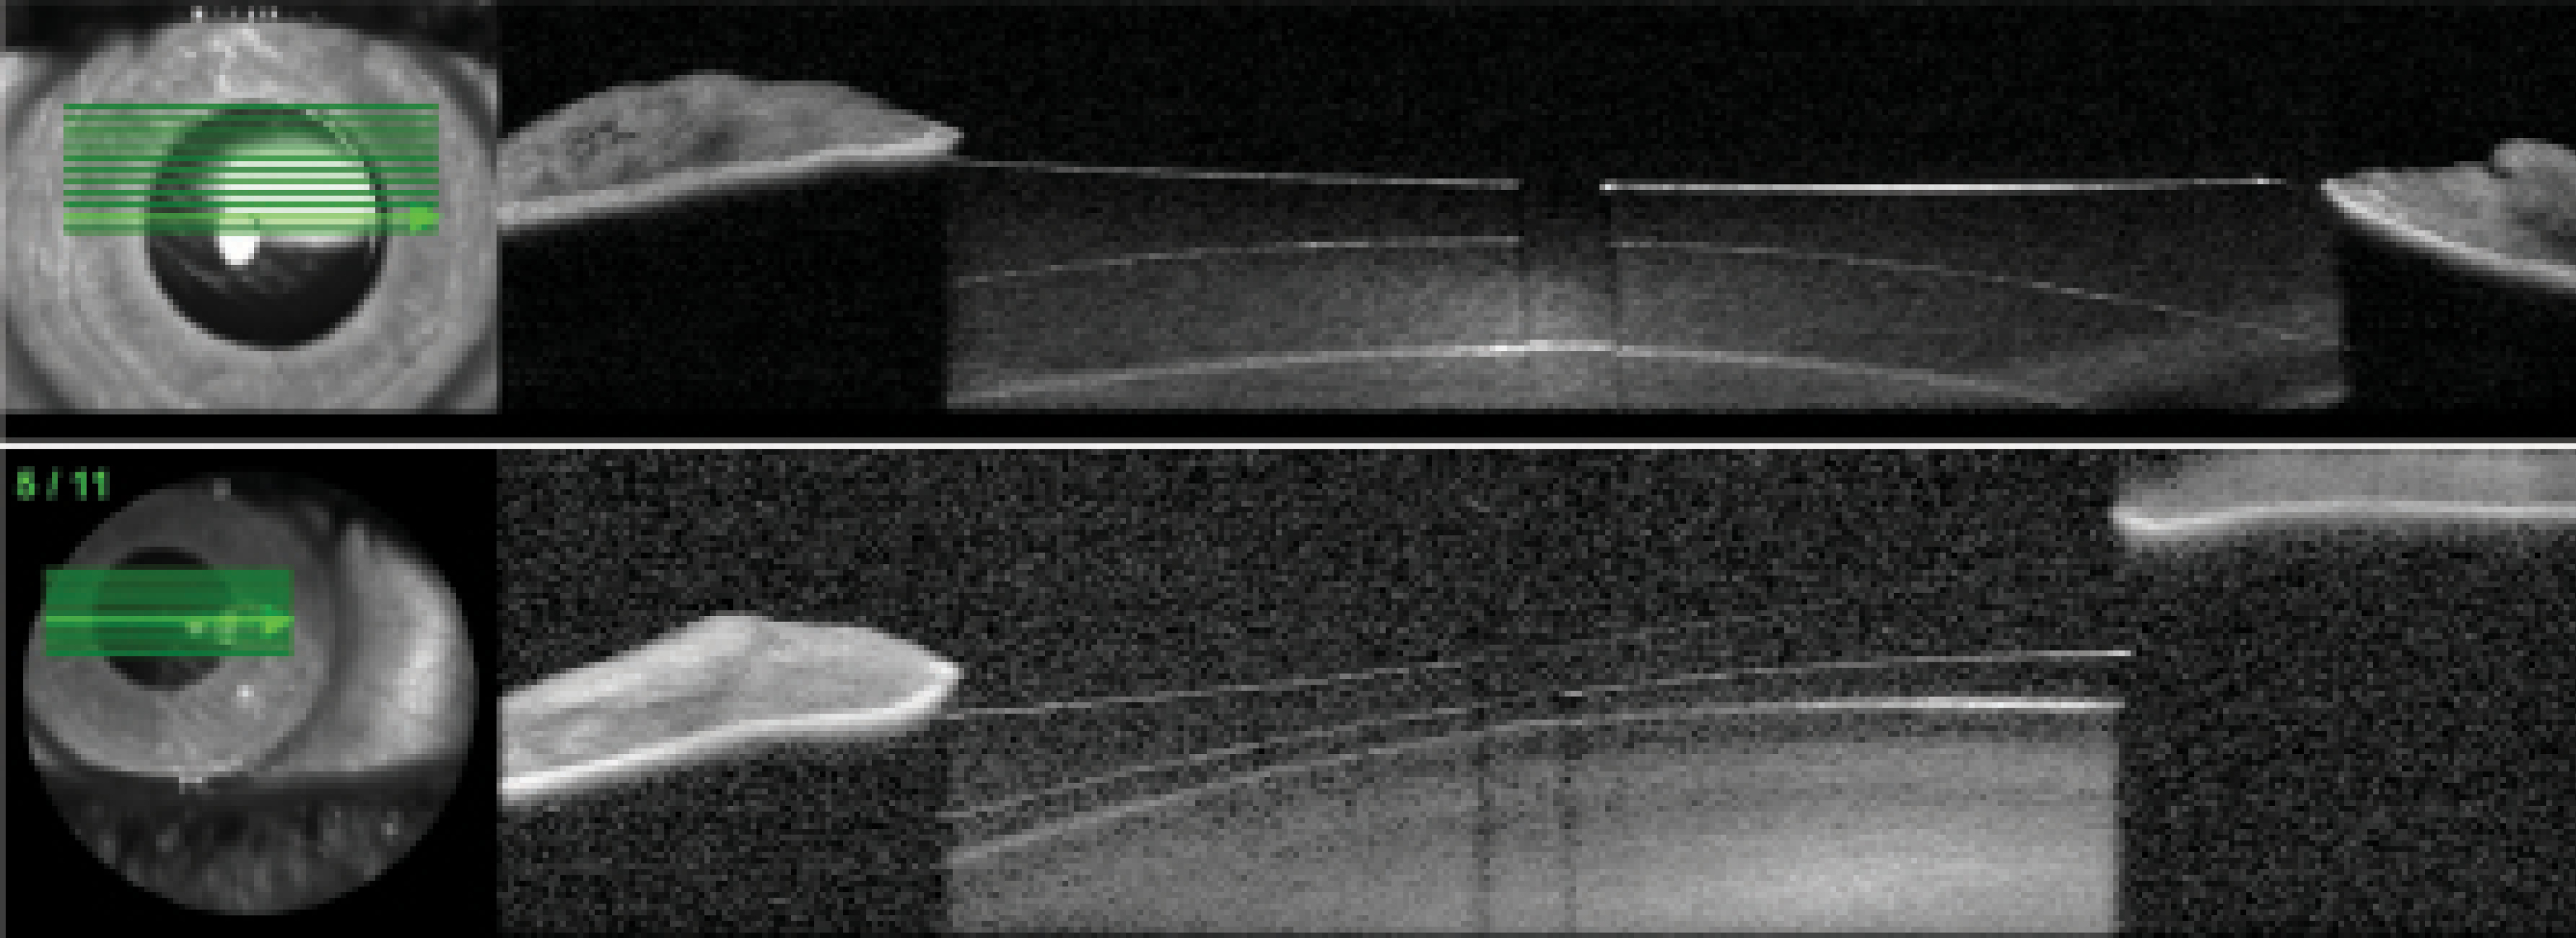

Figure 3. OCT (MS-39, A) and VHFDU (ArcScan Insight 100, B) scans of an eye that received an Evo Visian ICL.

Based on the case presentation, the central vault was measured, but this is not the minimum lens separation. The thickest portion of a highly myopic, concave ICL resides behind the iris and thus cannot be imaged by OCT. The only way of determining the physiologic minimum lens separation is with VHFDU because the thickest midperipheral lens zone is located behind the iris (Figure 3). OCT does not work in this situation because pupillary dilation to access the zone causes the ICL to move forward.12-14 Information on the minimum lens separation in an undilated physiologic state is required. VHFDU also allows the lens separation to be considered over the entirety of the midperipheral zone. The lens vault map shown in Figure 4 is derived from multimeridional scanning using the ArcScan Insight 100.